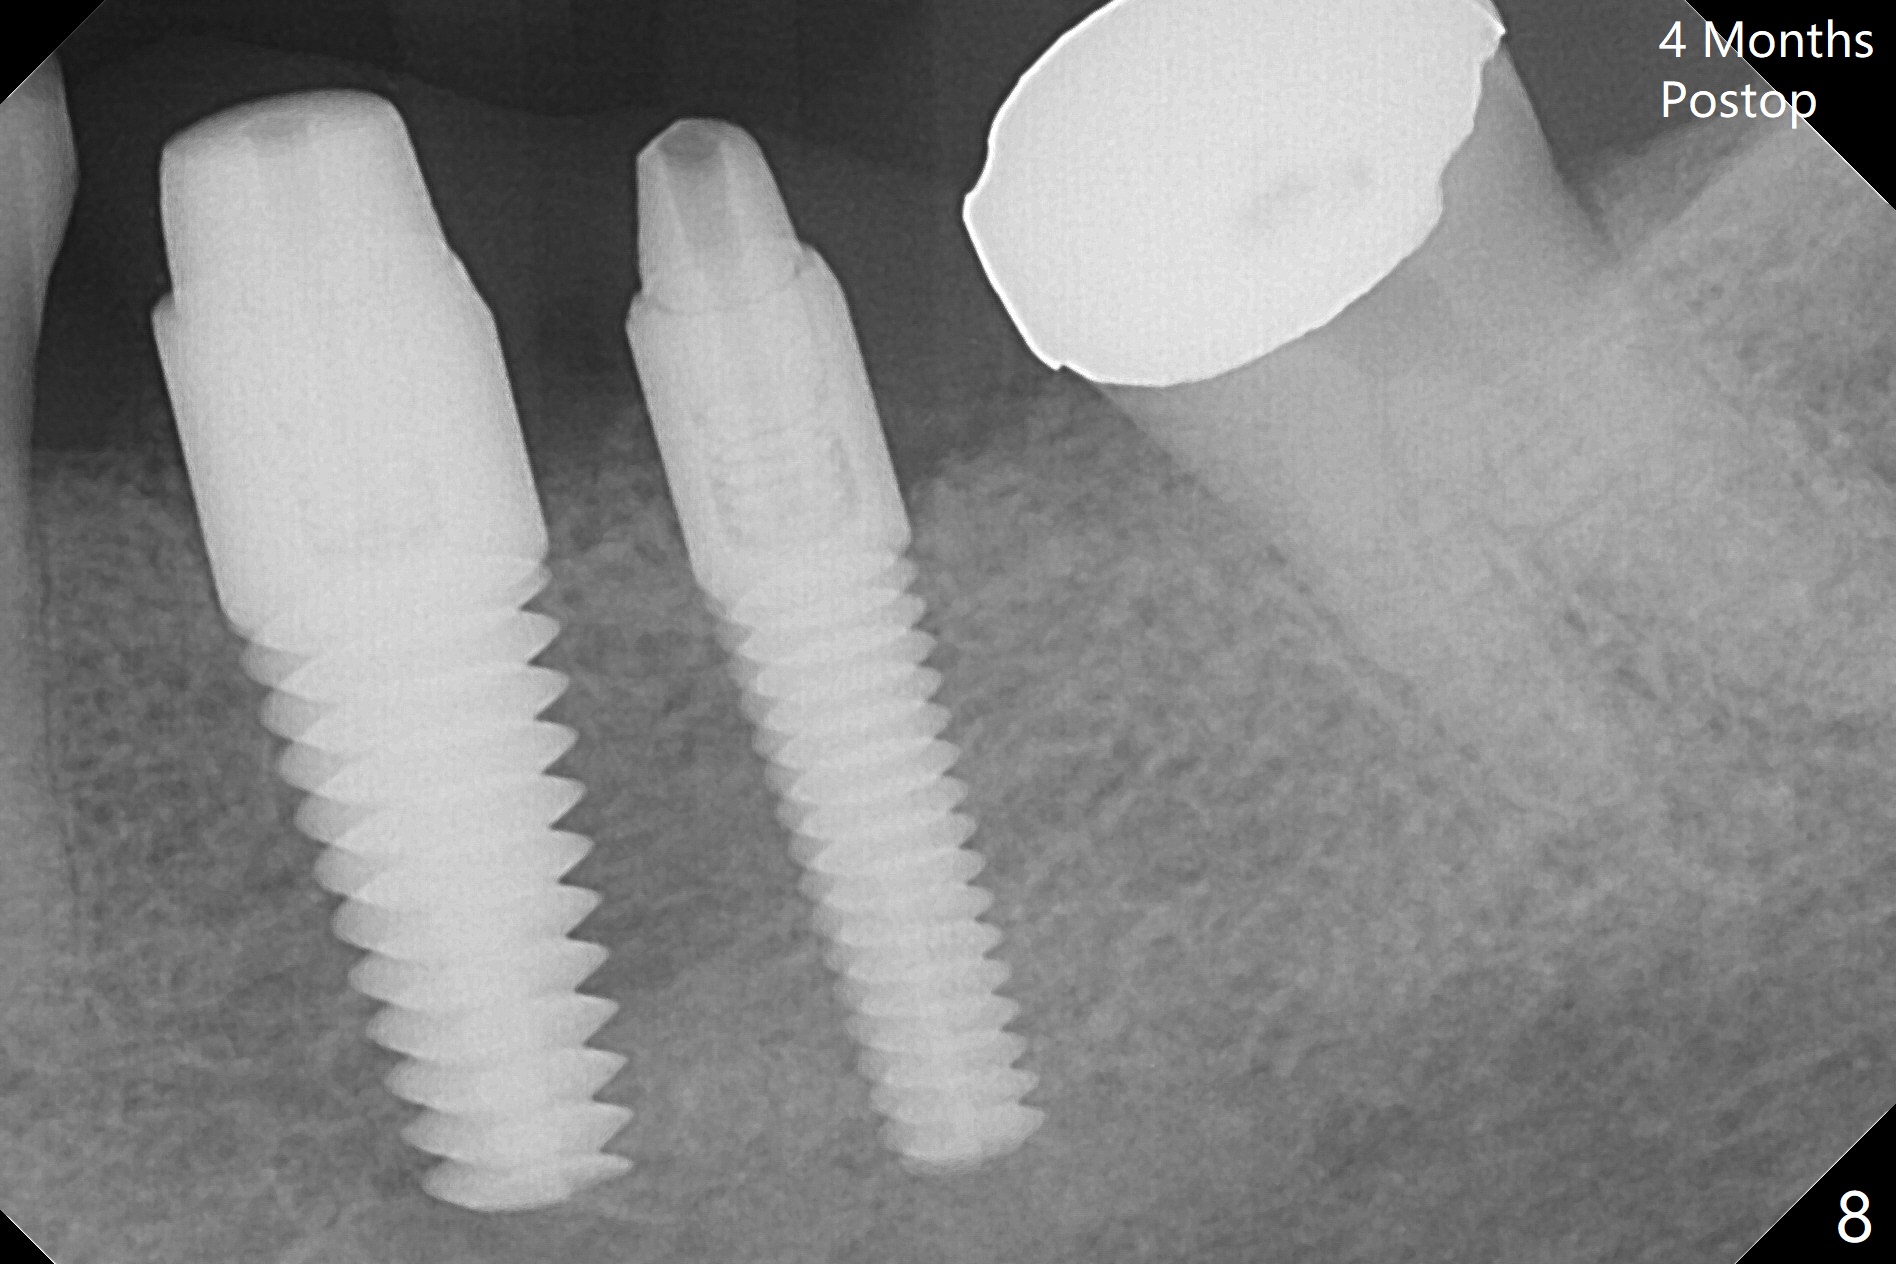

When the tooth #20 is extracted, the buccal and lingual plates are intact, but the apical lesion is deep. A PA is taken (Fig.1). Osteotomy will be established either along the long axis of the original socket (Fig.2 a line) or in the mesial slope (b line). Either osteotomy may damage the Mental Loop (red dashed line). To reduce the complication, osteotomy is being made by inserting 3.8 to 6 mm taps. In fact the 6 mm tap achieves stability (Fig.3,4), but it invades the buccal gap. When the tap is removed, the bottom of the socket is sensitive to probing with oozing from the socket. To reduce further compromise of the buccal space, Lindamann bur is used to remove the bone from the lingual and mesial plate, followed by placing a 6x17 mm implant with >50 Ncm (Fig.5). In fact the implant is placed shallower than the tap. When a 4x17 mm implant is placed at #19, there seems to be clearance from the Inferior Alveolar Canal (Fig.6). Postop there is no paresthesia. The buccal gap is <1 mm, which is filled with Vanilla Graft. After recementing the retainer (crown, C in Fig.7) at #18, periodontal dressing is applied to the sites of #19 and 20. Impression is taken 4 months postop with that of #15.